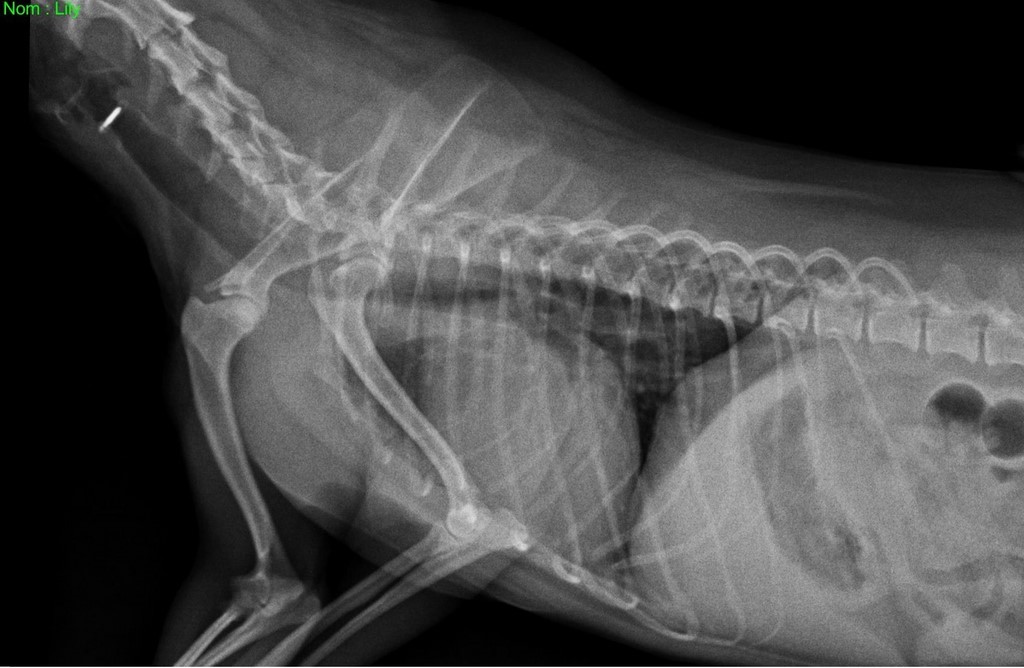

Radio de LiLy

Lily